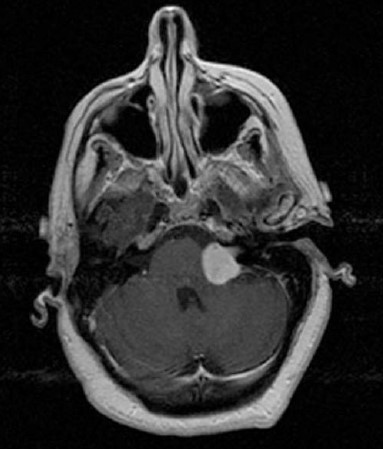

As seguintes afirmações são verdadeiras sobre o diagnóstico mais provável representado na figura abaixo, EXCETO:

As seguintes afirmações são verdadeiras sobre o diagnóstico mais provável representado na figura abaixo, EXCETO: